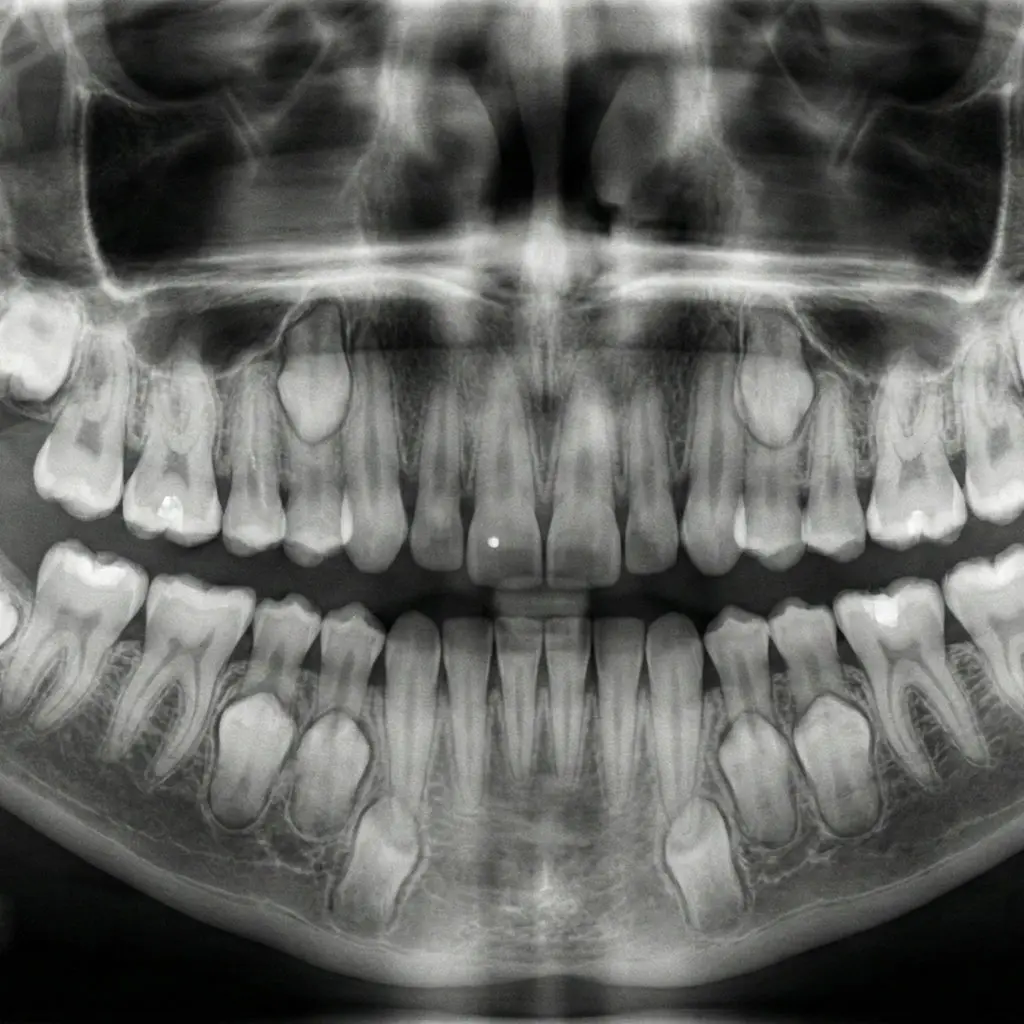

Monitoring Growth & Development

We don't just look for cavities; we monitor the growth of your child's jaw and the eruption of permanent teeth. We keep a close eye on habits like thumb-sucking or tongue-thrusting that can affect alignment.

By identifying potential orthodontic issues early (Interceptive Orthodontics), we can often guide jaw development, making future treatment simpler or even unnecessary.